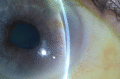

We report a very unusual presentation of primary intraocular lymphoma masquerading as anterior uveitis with atypical symptoms. A 68-year-old man, initially presented with a 4-day history of painless, left blurred vision. Examination revealed 2 or more anterior chamber cells, mutton-fat keratic precipitates and posterior synechiae. Treatment was initiated, the eye settled, and the patient was discharged. He re-presented 7 months later with hypopyon, a hazy cornea, fibrin deposits and a narrowed anterior chamber angle. Over the coming weeks, it became apparent that the temporal iris was thickened, involving the angle, and his intraocular pressure increased despite topical dorzolamide. Following advice from a tertiary centre and referral to a regional ocular oncology centre, a transscleral biopsy was performed and suggested a ciliary body melanoma. Enucleation was advised and performed, with histological examination revealing features consistent with an ocular diffuse large B-cell lymphoma not involving the optic nerve, sclera or cornea. This is the first ever published report of a case of ocular lymphoma masquerading in this way.